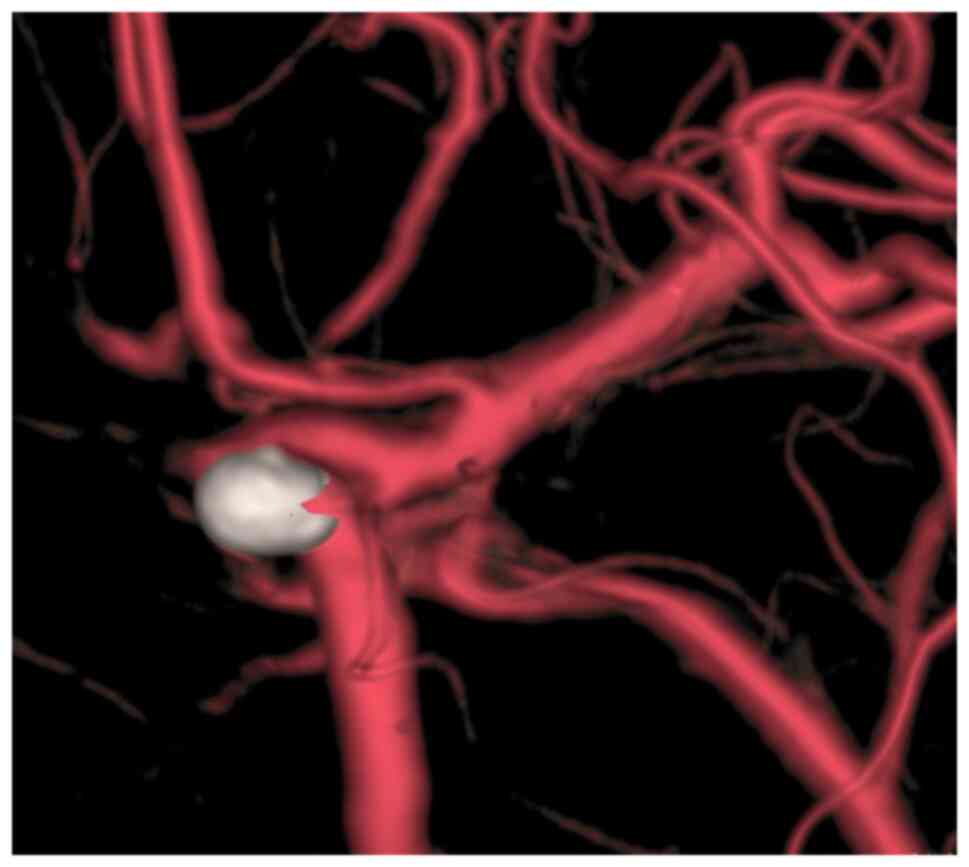

A 40-year-old male patient with a history of hypertension presented to the emergency department of Peking University People's Hospital (Beijing, China) in December 2019 with the complaint of headache for one day, sudden onset of nausea, vomiting and loss of consciousness for 4 h. Neurological examination revealed a Glasgow Coma Scale (GCS) score of 14 (E3V6M5). The patient was a habitual drinker and reported that no immediate family members had experienced any similar cerebrovascular events. The patient had no history of trauma, lumbar puncture or bleeding disorders. The patient was admitted to the emergency department of Peking University People's Hospital (Beijing, China). His blood pressure was controlled through the infusion of urapidil hydrochloride (2-4 ml/h) and his vital signs were stabilized using monitoring equipment and nimodipine administration (2-4 ml/h, 14 days), as described previously (6,7). Cranial computed tomography (CT) and CT angiography (CTA) were performed at the earliest. Brain CT and CTA (Fig. 1A and B) indicated diffuse SAH and an aneurysm in the right internal carotid artery. Thus, a digital subtraction angiography (DSA) examination was scheduled immediately. DSA revealed that the aneurysm was located in the inferior wall of the C5 segment of the right internal carotid artery, with the following characteristics: Aneurysm neck 3 mm and diameter 4x6 mm (Fig. 1C). The patient was placed under general anesthesia 9 h after the bleeding occurred and the intracranial aneurysm was embolized using a coil interventional embolization technique. DSA indicated that the patient's aneurysm was densely packed without contrast retention (Fig. 2A and B). The patient was diagnosed with a right internal carotid artery aneurysm and hypertension.

Figure 2

Digital subtraction angiography of the patient after surgery. (A) Skew map of aneurysm after embolization. (B) Side map of aneurysm after embolization. Digital subtraction angiography indicated that the patient's aneurysm was densely packed without contrast medium retention.

No apparent venous thrombosis was found by lower extremity venous ultrasonography 10 days after the surgery (Fig. 6A and B). To clear the SAH in the patient, lumbar spinal catheter drainage was performed on the first day after the operation. On the fourth day after the operation, the catheter was removed and a lumbar puncture was performed once a day for seven consecutive days to release the cerebrospinal fluid (CSF). The CSF became transparent and clear, while the patient was conscious and responsive. The muscle strength of both lower extremities returned to grade II two weeks after the operation. The patient was discharged three weeks after the operation and transferred to a rehabilitation hospital for further treatment. The patient was treated with cognitive and physical exercise in the rehabilitation hospital. The muscle strength of the patient's lower extremities was grade III one month after the operation and returned to grade V 60 days after the operation. The patient revisited the hospital for re-examination six months after the operation and his nerve function was found to be normal. A two-year follow-up cranial DSA indicated satisfactory embolization of the aneurysm (Fig. 7).

Figure 7

Digital subtraction angiography of the patient two years after the surgery. The image indicated satisfactory embolization of the aneurysm.